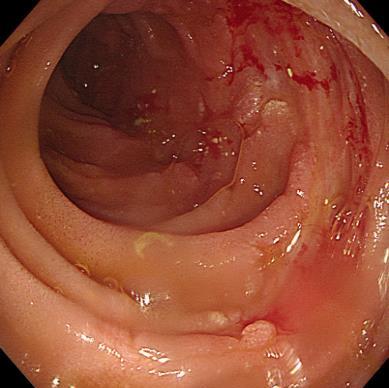

• 获得性免疫缺陷综合征合并马尔尼菲篮状菌导致肠道感染的内镜下表现(附6例报告)

2026, 32(3):84-88. DOI: 10.12235/E20250461

摘要 (32) HTML (27) PDF 3.50 M (26) 评论 (0) 收藏

摘要:目的 探讨获得性免疫缺陷综合征(AIDS)合并马尔尼菲篮状菌(TM)感染导致肠道感染的内镜下特征。方法 回顾性分析2022年11月-2024年10月于该院确诊为AIDS合并TM感染导致肠道感染的6例患者的临床资料。包括:临床症状、实验室检查、影像学检查、内镜检查和病理检查等。结果 6例患者中,男5例,女1例;发病年龄26~67岁;AIDS合并TM感染导致肠道感染患者的临床表现为:腹泻、腹痛、腹胀和恶心呕吐。其中,2例有消化道出血表现。实验室检查:6例患者外周血白细胞计数为(1.37~4.49)×109/L,血红蛋白计数为(67~99)g/L;CD4+T淋巴细胞为(1~52)个/μL,CD8+ T淋巴细胞为(61~321)个/μL,CD4+T淋巴细胞/CD8+T淋巴细胞比值为(0.01~0.18)。6例患者均行HIV RNA检测。其中,5例HIV RNA阳性。血培养:可见丝状真菌,报告显示为TM。影像学检查:6例患者CT结果可见肠系膜及腹膜后多发淋巴结肿大。内镜检查:6例患者内镜下均可见肠道病变。其中,十二指肠糜烂溃疡2例,结肠多发糜烂溃疡4例。病理检查:6例患者幽门螺杆菌(Hp)结果均为阴性,黏膜下可见成簇的小球形真菌孢子,符合TM感染;特殊染色:PAS(+),六胺银染色(+)。结论 当AIDS晚期患者出现消化道症状时,应警惕TM感染,病变部位常见于全结肠和直肠,亦可累及十二指肠,内镜下表现多为溃疡、糜烂和隆起性病变,形态表现无特异性;及时行胃肠镜检查、病理活检、特殊染色和免疫组化是确诊的关键。